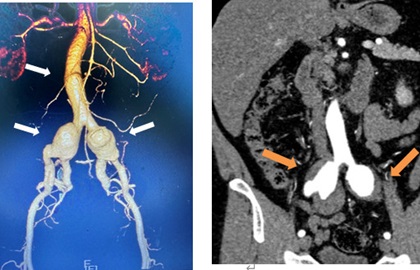

一连串,没有症状,体检意外发现!黄播 医生腹内“拆弹”!